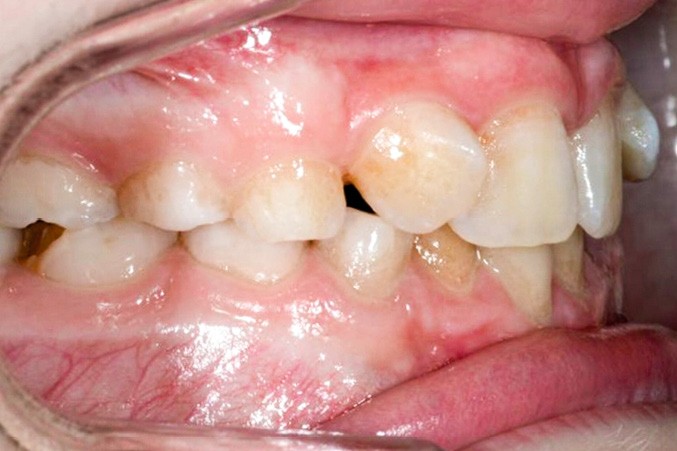

La patiente consulte à l’âge de 9 ans pour la malposition de ses incisives latérales maxillaires. Elle présente une occlusion de Classe I bilatérale sur un schéma normodivergent avec une dysharmonie dento-maxillaire en denture mixte. À l’arcade maxillaire, elle présente une endoalvéolie avec rotations mésiopalatines de 16 et 26.

Sur la radiographie panoramique, on observe une transposition des canines maxillaires en place d’incisives latérales, au contact des racines de 11 et 21.